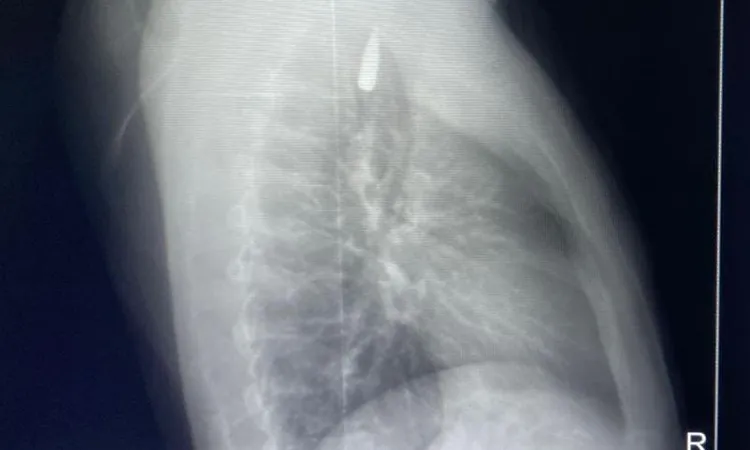

وقال الدكتور تامر عبد الله، عميد كلية الطب ورئيس مجلس إدارة المستشفيات الجامعية، أن المقذوف كان قد استقر على إثرها داخل تجويف القفص الصدري قرب الشريان الأورطي، وهو أكبر وأهم شرايين الجسم والمسؤول عن تغذية جميع الأعضاء الحيوية.

وأضاف أن الفريق الطبي، رغم دقة الحالة وتعقيدها، نجح في استخراج المقذوف بأمان بعد عملية جراحية نادرة استمرت عدة ساعات داخل المستشفى الجامعي الجديد، حيث خضع المريض بعدها للرعاية الطبية اللازمة، وحالته حاليًا مستقرة وتحت المتابعة الدقيقة من الفريق المختص.